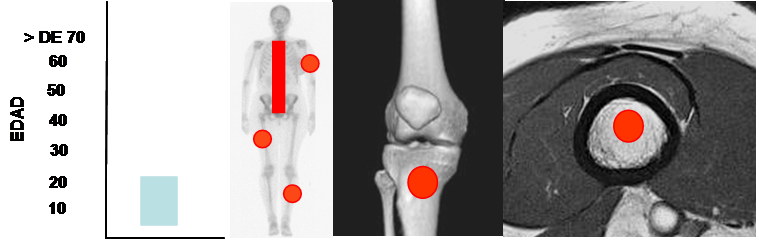

Fig 140. Quiste óseo aneurismático.

Mayor frecuencia entre los 5 y 20 años. Predominio en los huesos largos y las vértebras.

Lesión metafisiaria, de ubicación central.